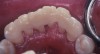

Fig 19. Preoperative lingual view before scaling and root planing.

Figure 19

Fig 20. Dental dam in place, teeth etched prior to placing a VPS blockout of the gingival embrasures.

Figure 20

Fig 21. Fast-setting medium-viscosity VPS impression material blockout of gingival embrasures (facial view) before placing the fiber-reinforced adhesive composite resin splint.

Figure 21

Fig 22. Lingual view of VPS blockout of gingival embrasures.

Figure 22

Fig 23. Completed Ribbond® THM fiber splint, teeth Nos. 22 through 27. The VPS blockout allowed for minimal finishing of gingival embrasure spaces.

Figure 23